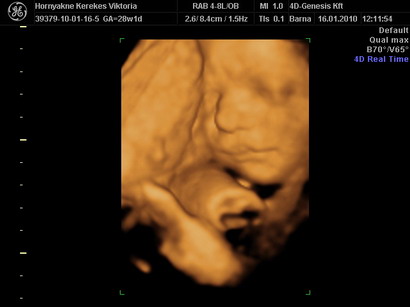

A nagy hír, hogy megint kis kukis van a pocakban. :-) Mindene megvan és egészséges, bár nem lett jó az AFP-m de megnéztek még egy értéket ami viszont jó lett + a genetikai uh. is jó. Így minden rendben van velünk.

Szerencsére a baba jól van (már 10.5 cm- a 15. héten vagyunk), most itt vagyunk anyukámnál vidéken és Ő figyel Márkra (bár néha úgy érzem anyira eleven, hogy néha 2 ember is kevés hozzá).

Az e heti UH-on azt mondták most már teljesen rajta van a lepény a méhszájon, szóval a helyzet csak romlott, de bíztattak, hogy remélhetőleg feljebb megy (a doki szerint ha a 24. héten is ott van akkor kórház végig), na ezt még elképzelni sem tudom hogy tudnánk kivitelezni...

Megbeszéltük a 4D-t is és az áprilisi fizunál megyünk. Igaz akkor már 30 hetes leszek, de látva néhány 30 hetes képet, amik nagyon szuperek lettek, nem aggódok :lol: :lol: